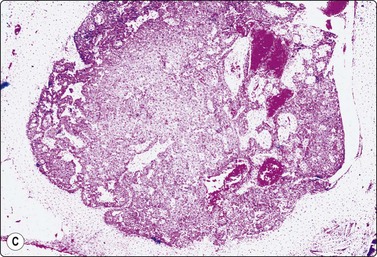

image image

Fig. 7.29 Benign phyllodes tumor

(A) Huge, slowly growing breast mass in a 40-year-old woman; (B) FNB smears were cellular, dominated by dispersed cells with bare oval or plump spindle nuclei (MGG, HP).